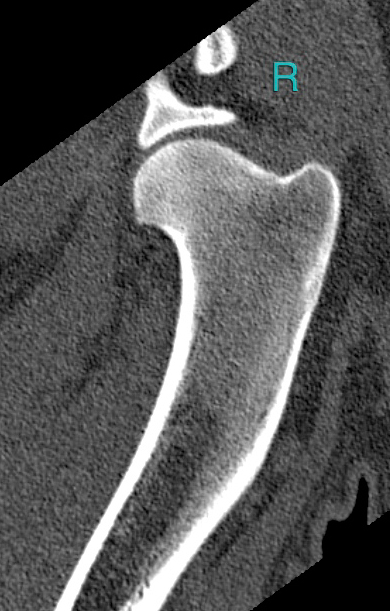

- I really don’t know what we’re looking at on this part of the ct scan. Other than it’s Pasha’s right.

While Pasha happily slipped back into a nap to my petting and stroking, the doctor showed me the scan and gave me his analysis of the imagery. To my astonishment, he said he’s seeing a ‘rather good’ set of shoulders and elbows (!), nothing in the way of arthritis (!!), and basically nothing in the way of elbow dysplasia (!!!). He did point to the same areas where our regular vet had diagnosed signs of elbow dysplasia and Fragmented Coronoid Process (FCP) out, but this doctor wiped them off the table as “nitpicking”. Well, insert dumbfounded look here. Our regular vet, who developed himself into a fine specialist surgeon for movement problems over the years, will probably still be on a well-deserved holiday break when I publish this article but I can hardly wait to discuss this scan with him! He’s the vet who made the x-rays in 2016 and last month and who called for arthritis/elbow dysplasia as a tentative diagnosis. I also still don’t have the radiologist’s second opinion at this point, which I’m equally curious about. Anyway, both the doctor and I swiftly moved on to this question: if Pasha has indeed good shoulders and elbows, than what is ailing him? The doctor reasoned it could very well be something in the softer tissues. Think a strained muscle or maybe a tear in a tendon or something. This sure sounded logical to me, but in the back of my head, I also thought about the back and neck hernias Misha and Bromley were diagnosed with during a previous life…